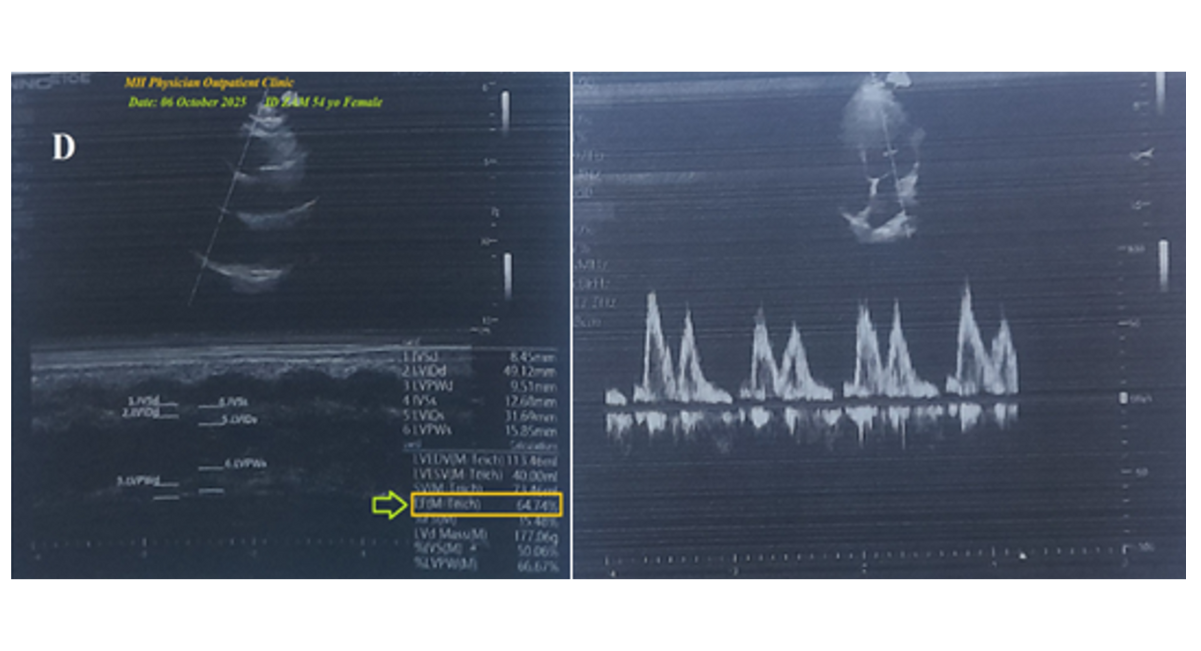

The echocardiography showed no abnormalities detected with a normal ejection fraction (EF: 64.74%) (Figure 2D). There is no more workup and radiological imaging.